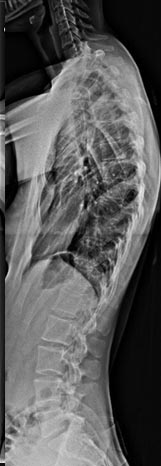

58 year old presenting with low back pain and bilateral leg pain especially when he stands for a few minutes or walks more than a few blocks.

Solid fusion 2 years postop